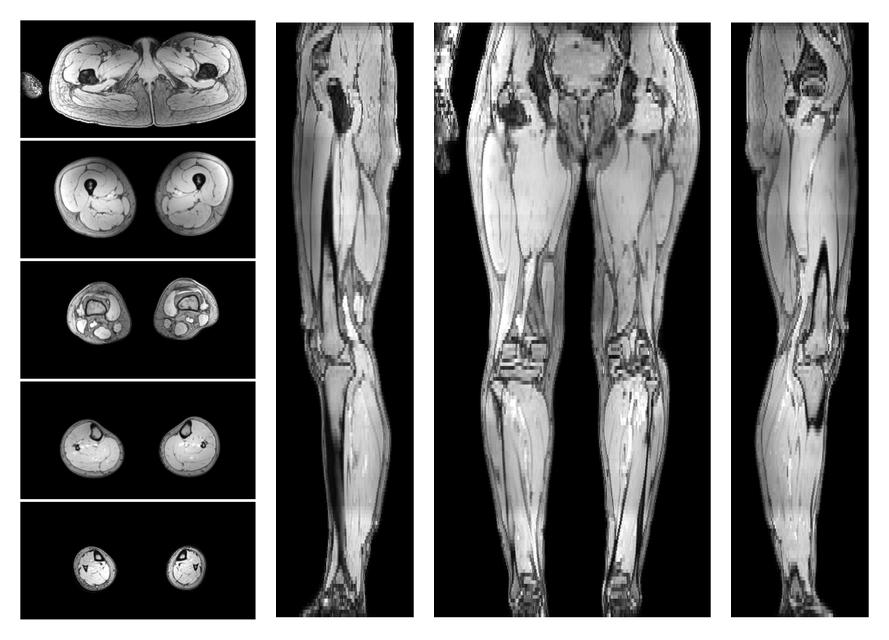

• Water only signal

The water part of the acquired multi-echo spin echo data.